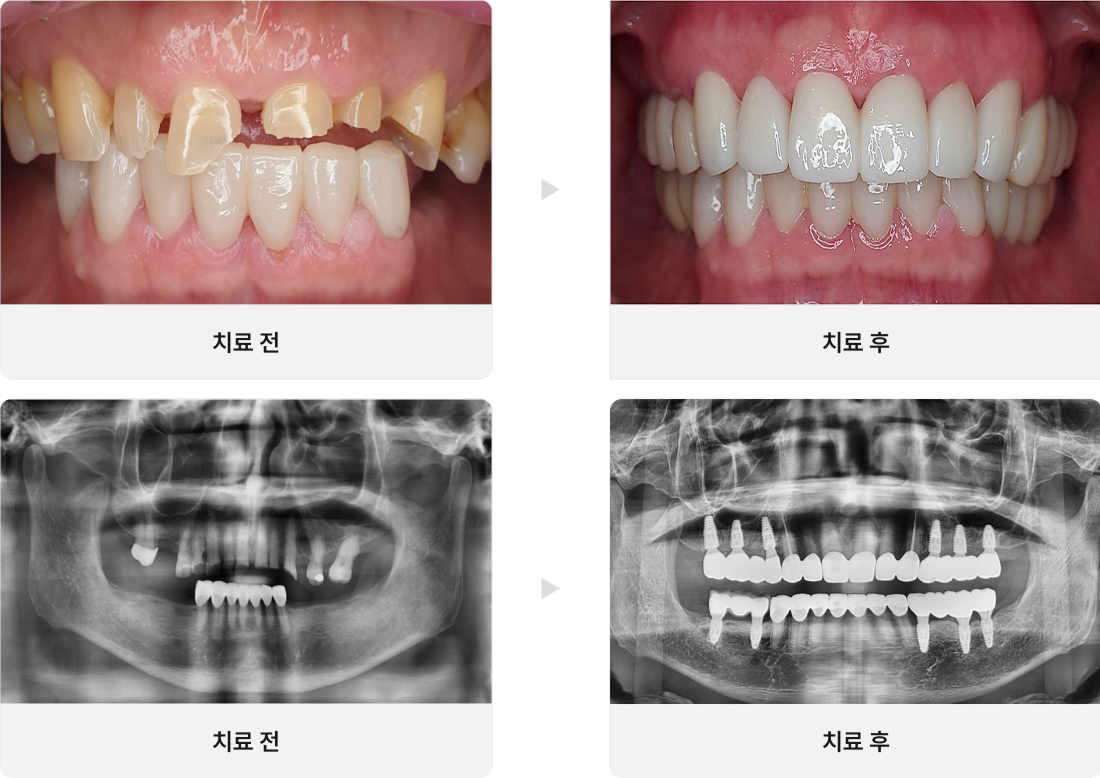

• CASE.01

심한마모 치아 살리기

• CASE.02